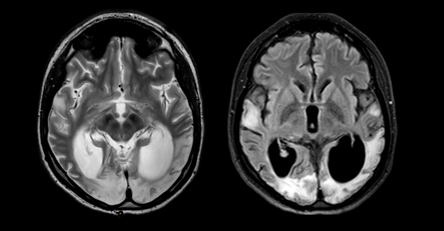

According to the father, from 2005 to 2009, adolescents had increased fatigue, leg edema, and body mass deficiency. On March 2, 2009, catarrhal symptoms (cough) and nosebleeds appeared on the background of an increase in body temperature to 39C. He was treated on an outpatient basis. On March 10, 2009, hearing deteriorated sharply (it was especially difficult to distinguish speech), auditory hallucinations and abundant salivation appeared. During his stay in the hospital, he was worried by a severe headache of migraine nature, simple visual hallucinations in the form of colored balls, spots. March 15th developed a generalized tonic-clonic seizure (GTCS). Performed MRI of the brain (Figure 1).

Figure 1 Brain MRI in T2VI and FLAIR modes (March 2009). Symmetric foci of increased MR signal intensity in the cortico-subcortical portions of the temporal lobes of both hemispheres are determined.